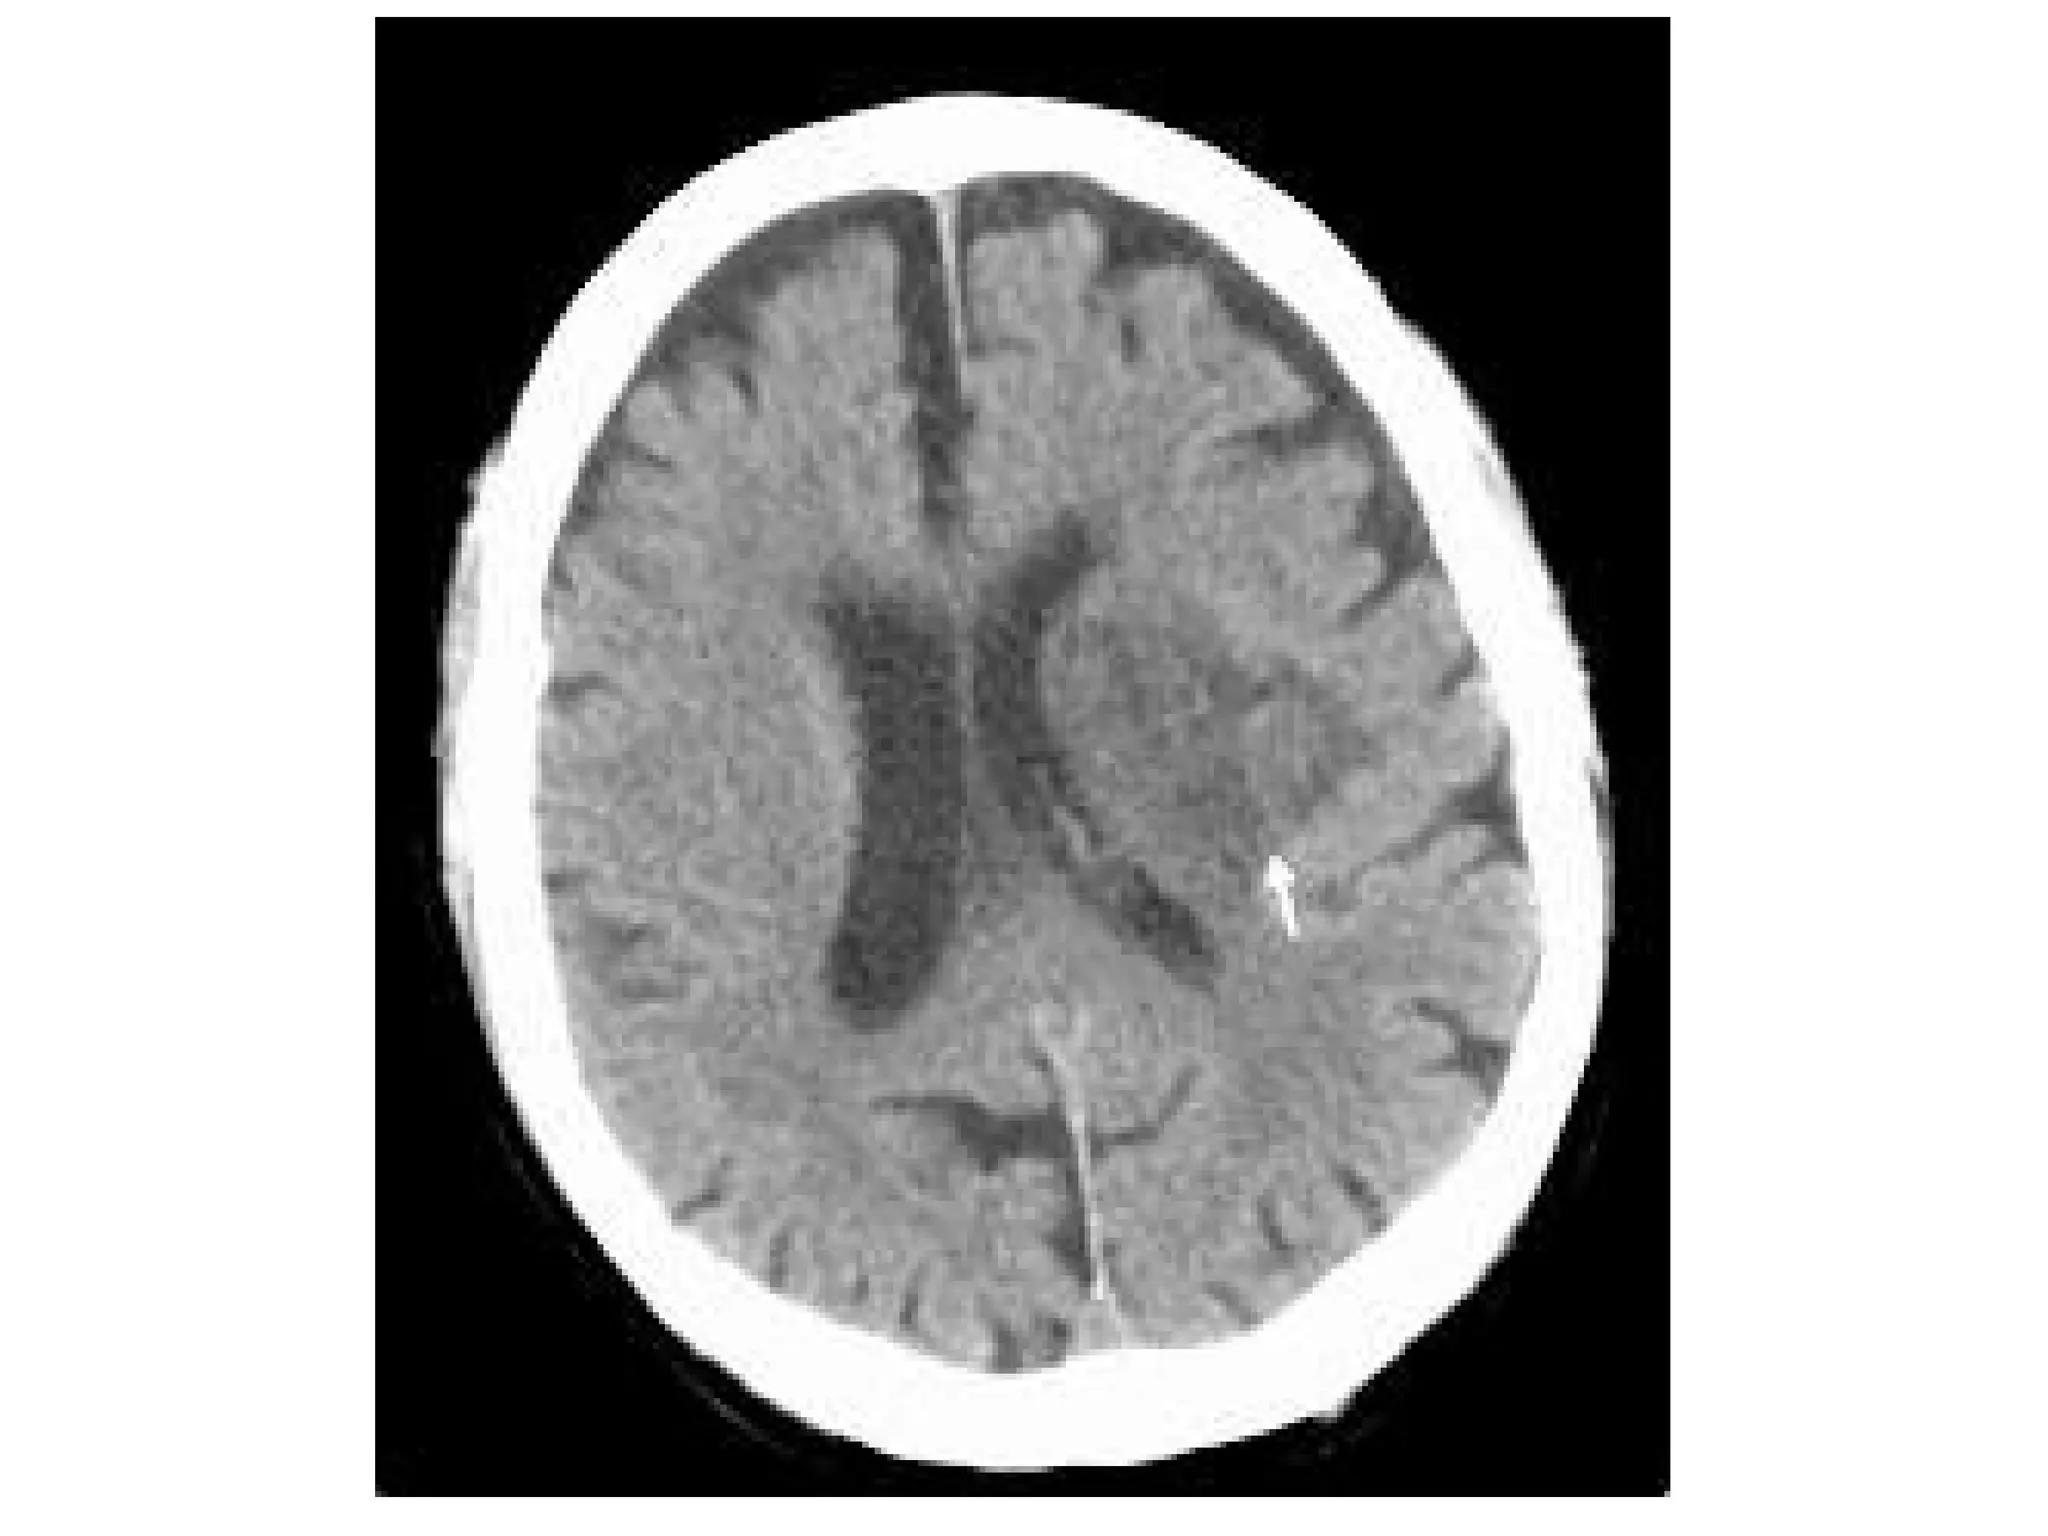

b) Generalized Mass Effect :

-Ventricular or basal cistern effacement +/-

midline shift (subfalcine herniation) or other

herniation syndromes : uncal , transtentorial

Midline Shift